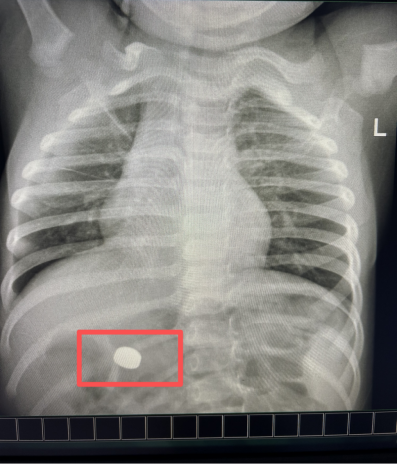

强台风“桦加沙”来袭,风雨交加。一位年仅一岁9个月的幼儿因误吞纽扣电池,被家属紧急送至我院急诊。

纽扣电池是婴幼儿常见的误吞异物之一,其危害不仅在于机械性梗阻,更在于电池在湿润的消化道内会发生泄漏,强碱性液体可快速腐蚀食管黏膜,可能导致灼伤甚至穿孔,处理必须争分夺秒。

消化内科医护人员接到急诊通知后,迅速完成病情评估,当机立断,为患儿开启院内救治绿色通道,确保检查、术前准备等环节一路畅通,最大限度缩短等待时间,同时,紧急联系麻醉科安排急诊手术。

患儿年龄小、食管结构纤细,这些因素不仅增加了内镜手术的操作难度,也对麻醉管理的精准性与稳定性提出了更高要求。

在麻醉团队的密切配合下,消化内科医师将内镜经口缓慢送入,精准定位异物后,以网篮稳妥套住电池,并平稳完整地将其取出。术后再次进镜观察,确认食管及胃黏膜情况良好,未见明显损伤、活动性出血或穿孔迹象。

整个手术过程顺利、耗时较短。取出电池后,患儿被安全送入病房进行后续观察。随着孩子转危为安,家属焦虑的情绪也逐渐平复。